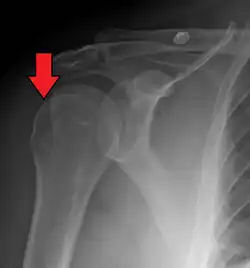

MRI of shoulder after dislocation with Hill–Sachs lesion and labral Bankart's lesion

Hill–Sachs lesion post-shoulder dislocation